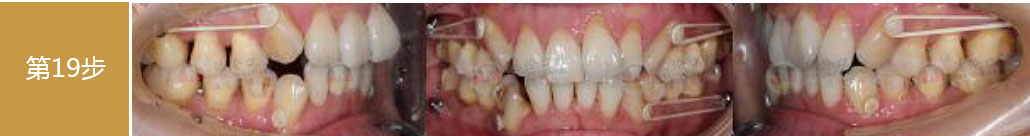

矯治前后對比

蛻變周期:上頜16個月,矯治效率提升30%,下頜12個月,矯治效率提升20%